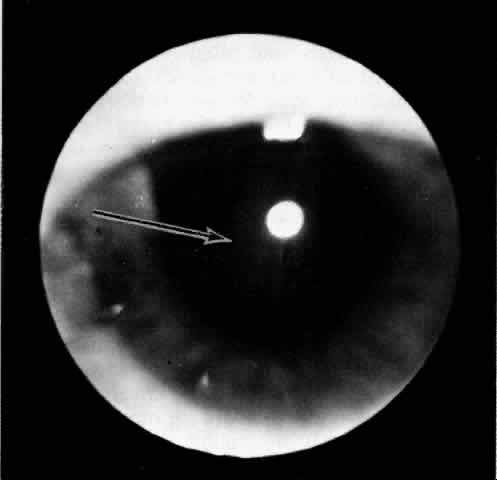

Ciliochoroidal effusions may have an annular, lobular (Fig. 4), or flat (Fig. 5) ophthalmoscopic appearance. Annular effusions occur around the ciliary body and peripheral choroid. Lobular effusions are large hemispheric detachments that bulge toward the center of the globe. Flat effusions are most often apparent in isolated peripheral choroidal areas, where local structures limit fluid extension. A local stimulus, such as a limbal incision, can lead to suprachoroidal edema, even in remote areas, by way of free dissection of fluid. Occasionally, patients will present with coexisting ciliochoroidal effusion and rhegmatogenous retinal detachment.23–25 The retinal hole may be hidden in the choroidal mounds. Such detachments tend to occur in older patients who have a history of previous ocular surgery.

Fig. 4. Clinical appearance of a lobular type of ciliochoroidal effusion.

Fig. 5. Flat ciliochoroidal effusion. The ora serrata is visible without scleral depression in a patient with Schepens-Brockhurst syndrome. The arrow indicates the ora bay.